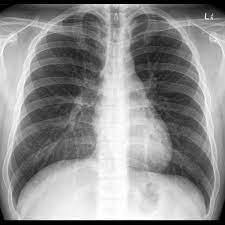

This is how a normal, healthy lung appears on an xray.

The black represents normal lung and filled with oxygen

The white triangular structure in the middle is the heart. It can barely be seen on the ARDS x ray above.